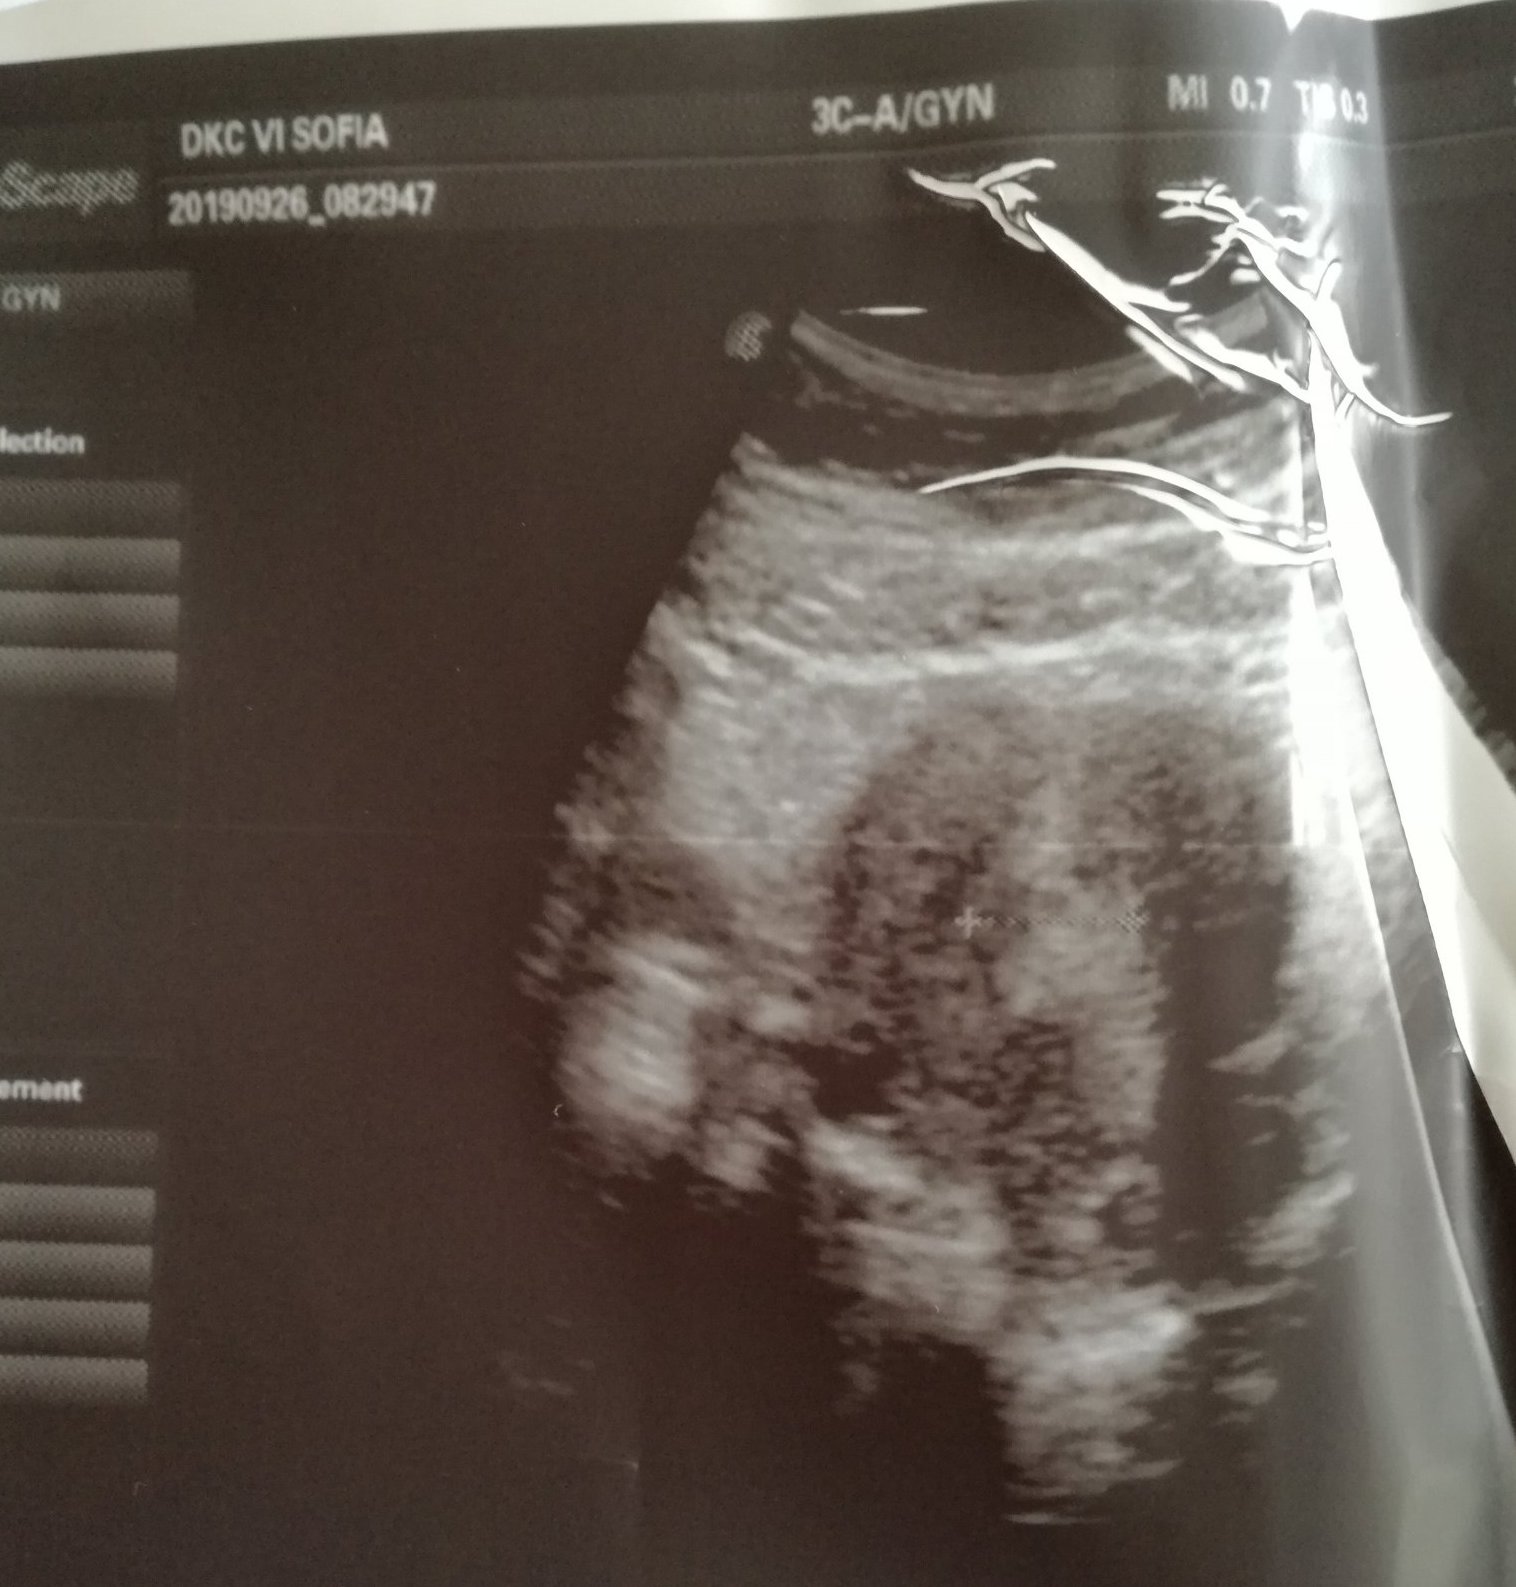

Аз бях днес да си взема резултатите - супер били , 1ва гр съм на цитото. Поне ми даде талон за ендокринолог и да изследвам прогестерон, естрадиол и FSH. Интересното беше на ехографа, че каза, че имам много лигавица и иска да ме види след цикъла. Нямам кисти никакви, но видя някаква точка. И аз я видях доста отчетливо точката на монитора, и като каза , че при бременност се образува много лигавица, направо няма да ви кажа как ми прескочи сърцето с два удара. Да , ама няма как, няма шанс. Казах му , че ми е 20ти ден от цикъла и че на ММ операцията е била на 5ти ден от моя цикъл и от 13ти ден реално имаме опити. И той се съгласи, че е малко вероятно. И аз питах като не е Б , като не е киста каква е тая точка и той вика лигавица. Много странно ми стана. Сега си гледам снимката от ехото и точката хич не я виждам толкова отчетливо както на монитора. Питах и за гърдите защо ме болят, каза че било нормално от хормоните.